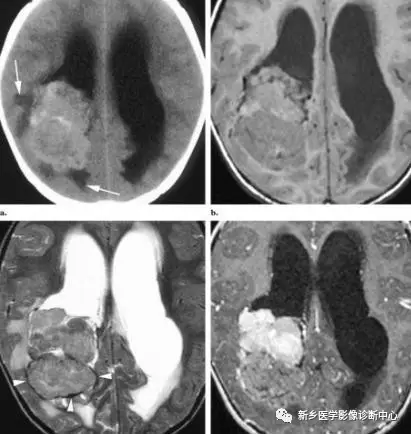

腫瘤常呈類圓形,邊緣常為絨毛顆粒狀、乳頭狀、小結節狀等,凹凸不平;CT上呈等或稍高密度。MRI上T1WI多呈等或稍低訊號,T2WI多呈高訊號。可分泌腦脊液,引起全腦室擴張,不同於其他腫瘤壓迫引起的區域性腦室擴張。

產生腦脊液遠遠超過正常每天450ML腦脊液量腫瘤中心位於脈絡叢。周圍腦脊液多,腫瘤可完全浸泡在腦脊液中。其內顆粒狀、乳頭狀混雜訊號為其特徵性表現。腫瘤內可見囊變,出血或鈣化。

鈣化為散在局灶性針狀,也可累及整個腫塊。有血管蒂附於脈絡叢。脈絡膜動脈增粗。富血供,平掃可見血管流空。由於脈絡叢含有較多穿支血管且無血腦屏障,增強掃描實性部分及囊壁均明顯強化。